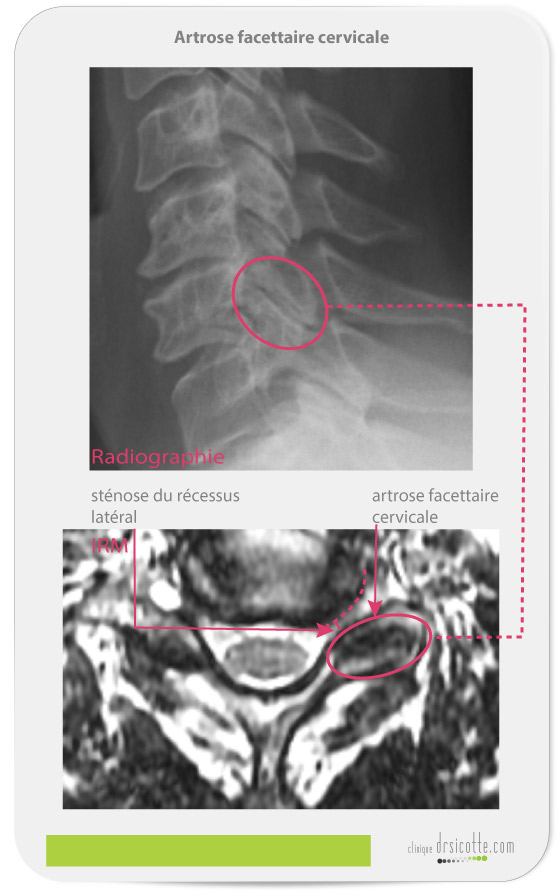

La sténose du récessus latéral cause une douleur au bras ou à la main. Les symptômes de l’arthrose cervicale facettaire avec sténose du récessus latéral sont :

Picotement, brûlement, bourdonnement, froideur, engourdissement intermittent dans une main.

Les symptômes qui varient selon la position de la tête : faiblesse musculaire, bras, main et épaule